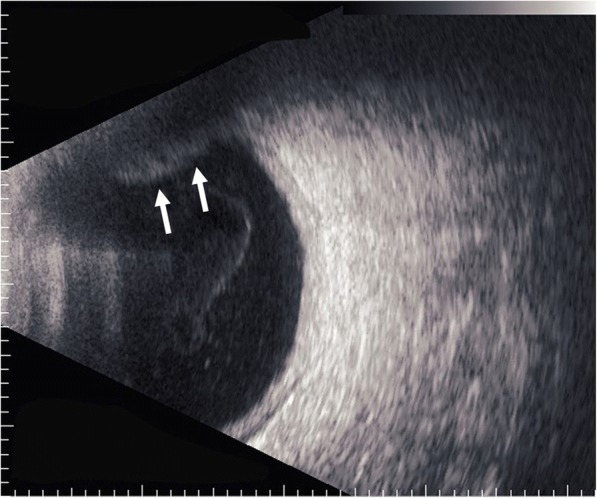

Fig. 4.

B-scan ultrasonography showed that the sclera was thickened and that the lesion seemed to have high internal reflectivity (arrows)

In regard to the follow-up treatment course, we initially increased the frequency of the instillation of steroid eye drops and added immunosuppressive eye drops. However, those drugs were ineffective, and the vitreous opacity gradually increased. Thus, we increased the amount of oral prednisolone to 20 mg per day in November 2014. Subsequently, the eye redness and vitreous opacity gradually disappeared within approximately 2 weeks, her VA slowly improved, and there was no remarkable fundus abnormality in the right eye at each examination. However, uveitis accompanied with moderate ocular pain relapsed (Fig. 2a, b), and fundoscopic examination revealed an intraocular elevated whitish lesion at the superior nasal retina of her right eye in November 2015 (Fig. 3a, b). We did not observe any restricted motility accompanied with eye movement. B-scan ultrasonography was also performed, and revealed that the sclera was thickened and that the lesion seemed to have high internal reflectivity (Fig. 4). Although the patient underwent a magnetic resonance imaging (MRI) scan for a differential diagnosis, it was difficult to distinguish whether the lesion was a granuloma or a tumor. Ultrasound biomicroscopy (UBM) and high frequency B scan might have been useful to distinguish between a tumor and granuloma, however, those examinations were not available at that time.